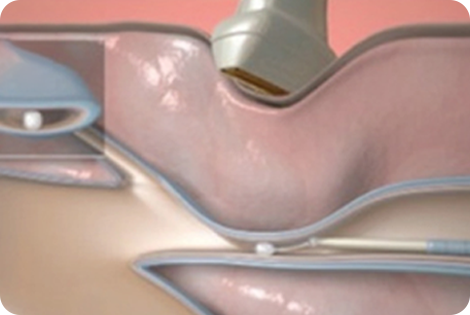

베나실은 인체 친화적인 의료용 접합제를

질환이 있는 원인 정맥에 주입하여

정맥을 폐쇄하는 하지정맥류 치료 의료기기입니다.

얇은 카테터(관)을

혈관에 삽입합니다

인체 친화적인

의료용 접합제를 주입합니다

해당부위를 압착합니다

혈관을 폐쇄하여 붙입니다